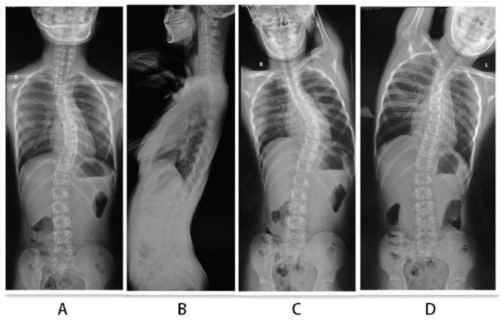

2. طريقة الانحناء على نقطة دعم محددة (Fulcrum Bending): يتم دعم العمود الفقري عند نقطة معينة والانحناء حولها.

• تعطي نتائج دقيقة للانحناءات الصدرية.

• تساعد الأطباء على توقع مدى تصحيح الانحناء بعد العلاج.

• الانحناءات المتوسطة: الانحناء الجانبي أثناء الاستلقاء يعطي نتائج أدق.

• الانحناءات الصدرية: طريقة النقطة الداعمة (Fulcrum Bending) هي الأنسب.